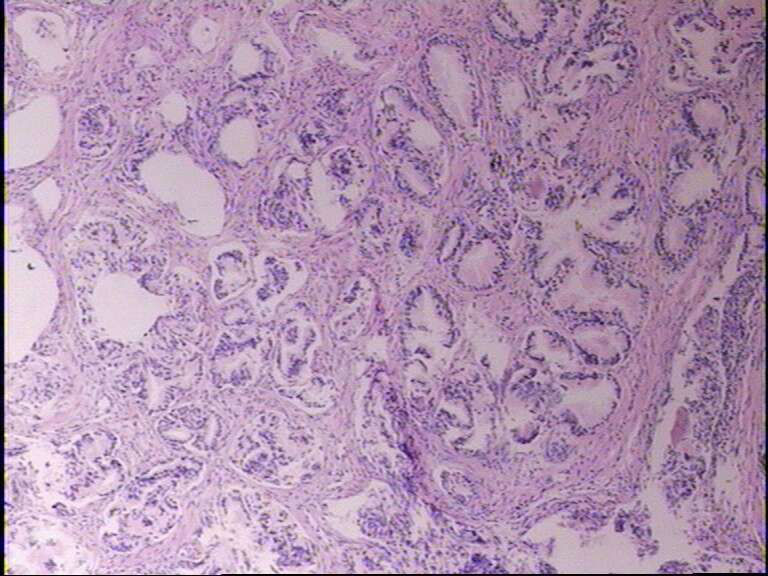

男72岁,排尿困难一年

• 前列腺图1

图1

前列腺良性增生,最好做P5O4S 、P63 、34βE12

良性前列腺增生症。

结节性增生

符合前列腺良性增生